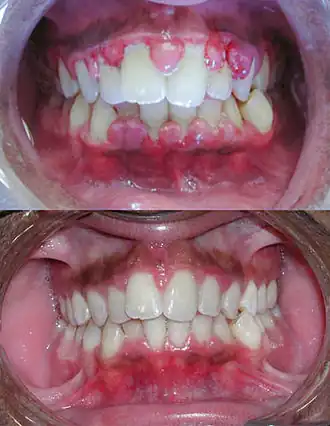

![]() Тяжелая форма гингивита до (вверху) и после (внизу) тщательной хирургической обработки раны зубов и прилегающих тканей десен | |